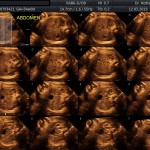

- Crecimiento fetal.

- Las estructuras anatómicas fetales: diagnóstico de Malformaciones Estructurales de aparición tardía (displasias esqueléticas, alteraciones cardiacas pequeñas, alteraciones la vía urinaria y obstrucciones intestinales.

- El escenario Gravídico: Placenta, liquido y Anexos.